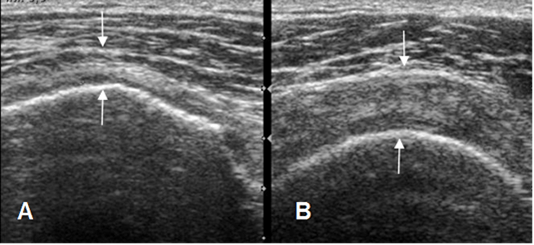

Pruebas complementarias.